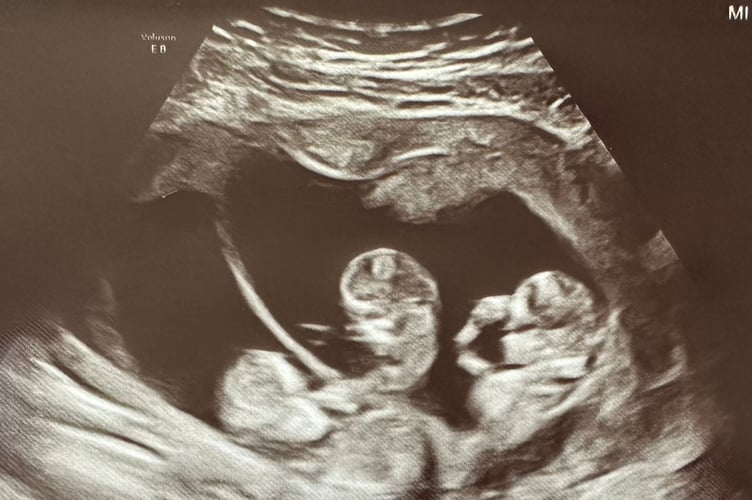

At eight weeks, the couple decided to have a private scan as Hannah's parents were visiting and they wanted to tell them in person that they were going to be grandparents.

During the scan, the sonographer's hands started to shake and Hannah and Chris immediately thought the worst but she revealed the pair were expecting triplets.

Hannah said: "We didn't know what to expect at the scan - it felt like the specialist was taking ages.

"When the sonographer stopped she turned to us and she was shaking, we were expecting bad news.

"She had never been in the position before that she found triplets, it was a big moment for her and an even bigger moment for us.

"I had a nervous laugh, I started laughing right away. She turned to the screen and pointed out the different places where the babies were.

"I burst out crying, there were a lot of emotions."

During the pregnancy, she had more than 20 pregnancy scans to make sure the triplets were progressing well.